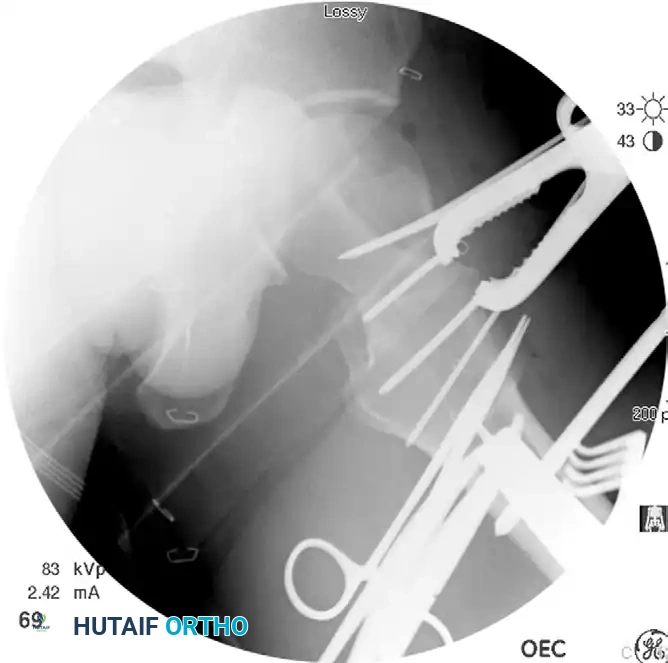

Anatomic reduction achieved. A Farabeuf reduction clamp is utilized to gain and maintain compression across the femoral neck fracture prior to hardware placement.

Confirm the reduction visually through the anterior approach and radiographically via AP and lateral fluoroscopy. The reduction must be perfect before proceeding to fixation.